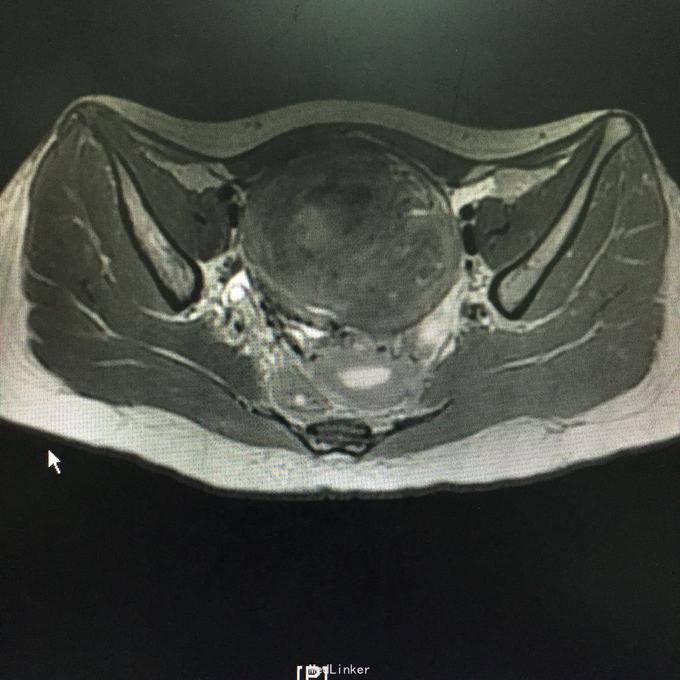

查体:子宫前位,增大如孕12周,可触及一直径约10cm包块,实性,表明光滑,似与子宫相连,活动度科,无压痛。入院后查肿瘤标志物未见异常。彩超是:子宫右前方见一个类圆形低回声团,按压似与子宫右相对运动,大小108*105mm,边界清,内部回声不均匀,见栅栏样衰减。盆腔MR示:子宫前方巨大占位,考虑间叶源性肿瘤与浆膜下子宫肌瘤鉴别。

入院诊断:盆腔包块查因。术中见,子宫前位,正常大小,子宫前壁浆膜下肌瘤,大小约10*10cm,表明光滑,蒂部宽约3cm,近宫底,子宫质地软,活动好,双附件未见异常,予以行子宫肌瘤剔除术,术中冰冻示:子宫平滑肌瘤,部分间质水肿。